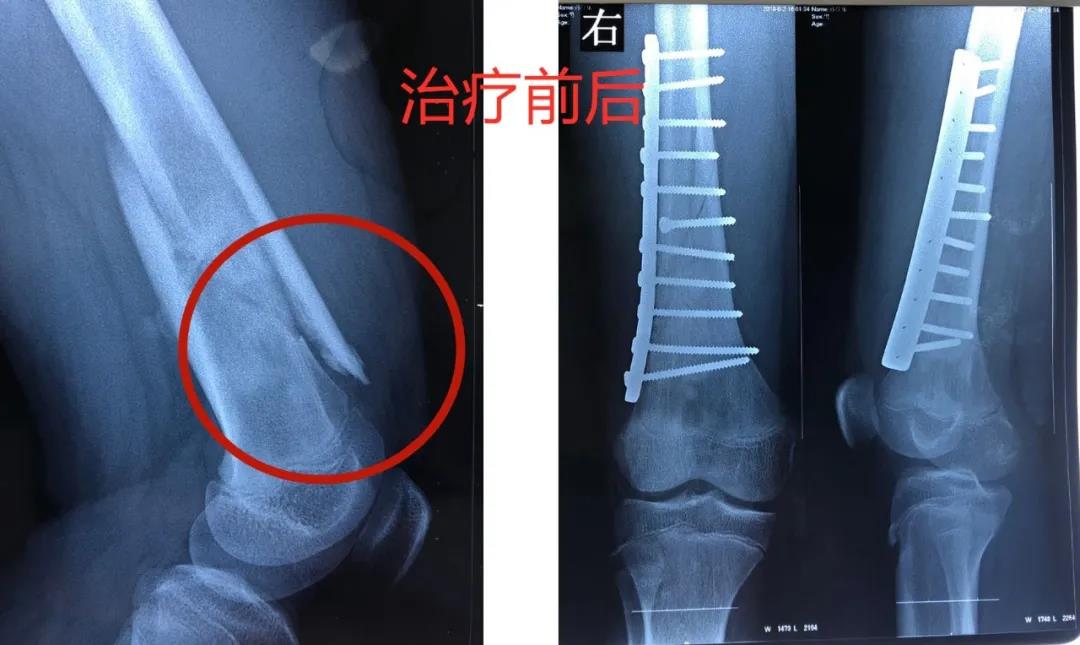

12岁的男孩儿浩浩,在学校上体育课,扭伤后突发右侧大腿剧烈疼痛,不能活动,被家人紧急送到医院,当地医院拍片后提示右股骨中下段斜行骨折。随后,医院按照一般骨折处理。

但在手术中,医生发现髓腔内“不正常”,留取了标本,经河南省肿瘤医院会诊提示为骨肉瘤。

无独有偶,11岁的女孩儿晨晨,假期在家和小伙伴玩耍时,不慎摔倒,本来家长并未在意,但晨晨直喊疼,且大腿活动障碍。在当地医院检查确诊为左股骨中下段骨折,随后医生对病灶刮除,按照一般骨折处理。

当地医生将病理组织送河南省肿瘤医院病理会诊,提示为骨肉瘤。

消息犹如晴天霹雳,但更让两个孩子的父母痛苦的是,“由于按一般骨折做了手术、打了钢板和钢钉,破坏了肿瘤外面原本相对完整的包膜,这个自然屏障一旦被破坏,肿瘤细胞就会‘污染’周围组织,以后想再切干净就更困难了。”河南省肿瘤医院骨与软组织科主任、主任医师姚伟涛表示。

最终,王鑫医师组为浩浩、晨晨两位小朋友选择了新辅助化疗,待疼痛症状缓解后,手术取出钢板、钢钉,并通过扩大切除手术,完整切除长瘤子部分的股骨,并进行体外灭活,搭配肿瘤型组配人工膝关节置换,达到了既完整切除肿瘤,又保全了孩子肢体功能的目的。